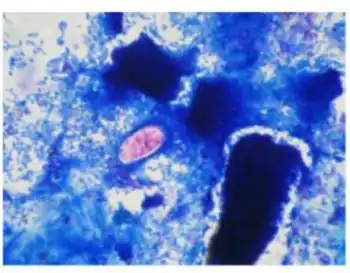

| strained oocyst of Cystoisospora belli | |

A fully mature (sporulated) oocyst of genus Isospora is a spindle-shaped body that has two sporocysts that contain four sporozoites each.[4]

The oocysts of Cystoisospora belli are long and oval shaped. They measure between 20 and 33 micrometers in length and between 10 and 19 micrometers wide.[5]